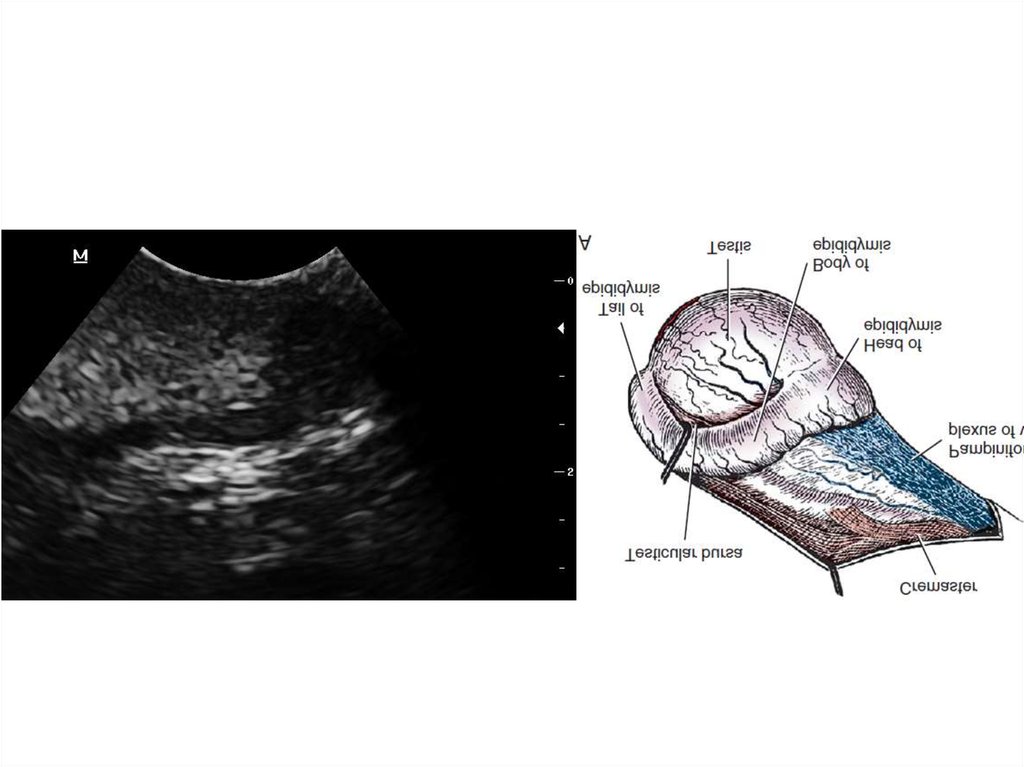

Оцениваем

Размеры

Границы: ровность, четкость

Капсула: лоцируемость

Паренхима: однородность, эхогенность,

эхоструктура

Evans, Lahunta; 2012